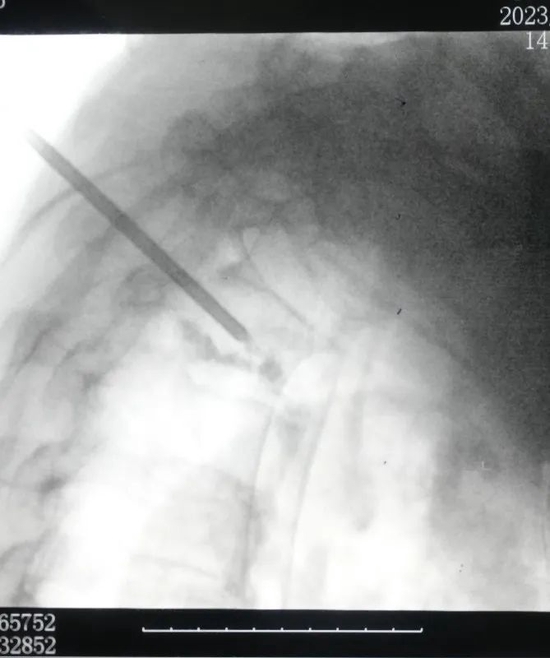

最终,骨科二病区与麻醉科、手术室通力合作,完善术前准备、制定周密计划,医疗团队于2月16日成功为患者行手术治疗。

术前VS术后

这一手术的成功,展示了骨科二病区整体医护团队的高超水平和精湛技艺,帮助期颐之年的老人远离高位截瘫的危险。同时也再一次证明了高龄在禹城市人民医院不再是骨科手术的“禁区”。